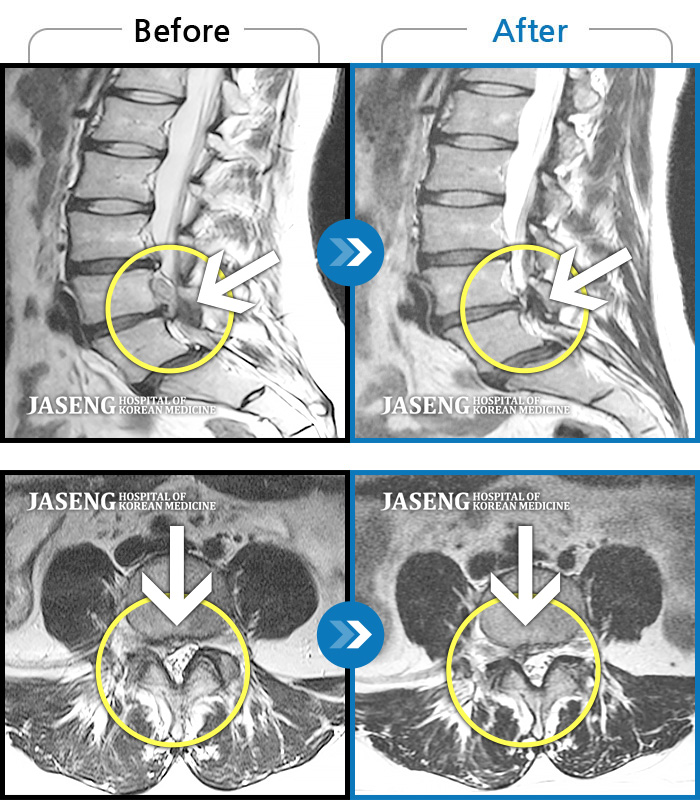

Before

After

환자에게 사전 동의를 받아 동일 조건에서 촬영되었습니다.

개인에 따라 치료 후 부작용이 발생할 수 있으니 의료진과 상담 후 치료를 진행하시기 바랍니다.

허리 통증 및 우측 엉치 다리에 통증

허리 골반통증 및 우하지 방사통